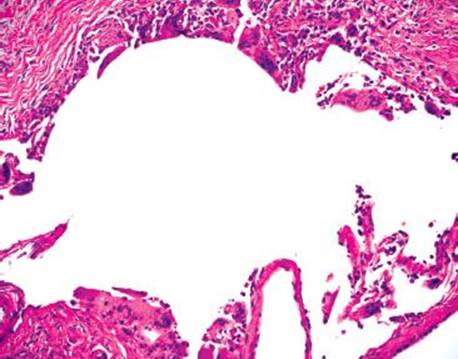

Figure 4.262 PCI. Highest power shows the bland features of the foreign body giant cells lining the empty spaces.